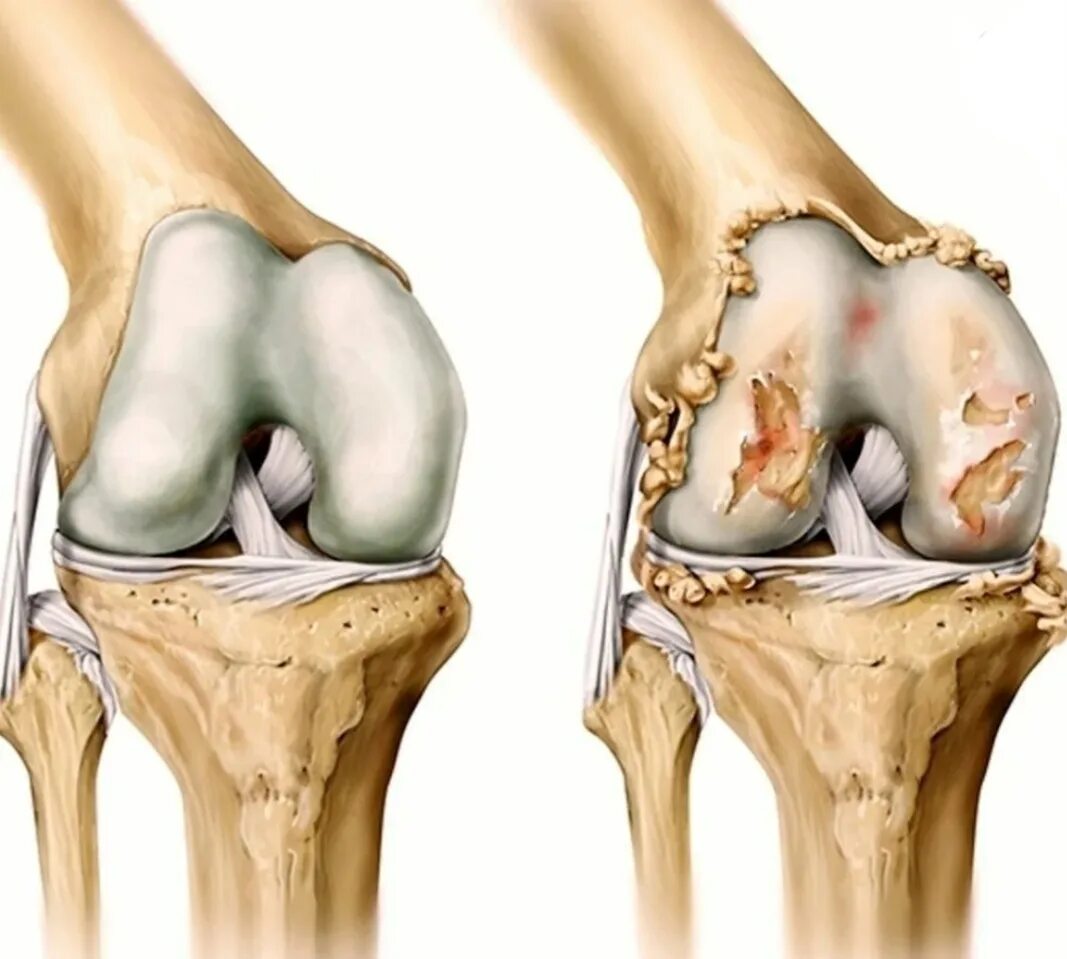

Остеоартрит 2025